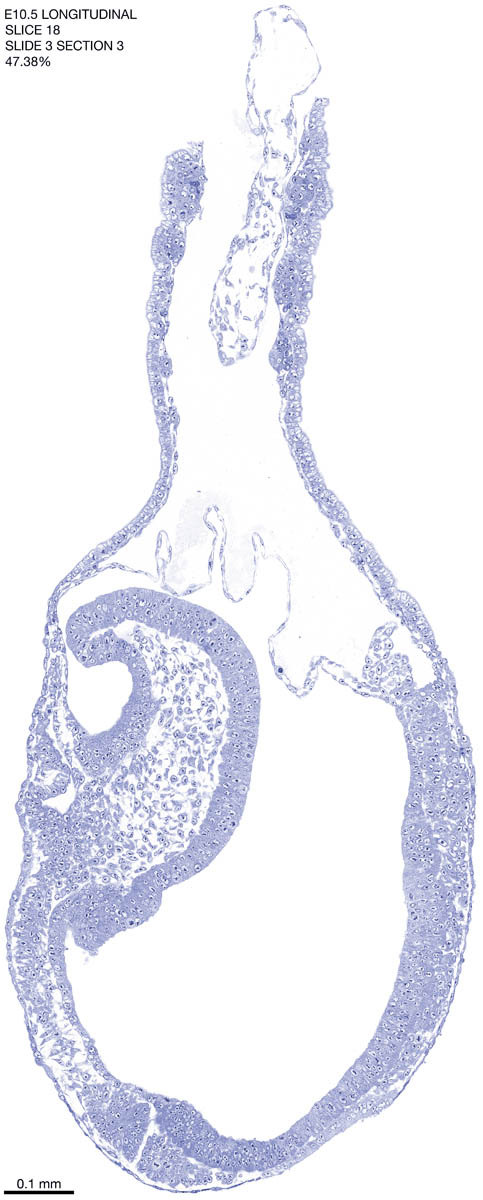

E10.5 Longitudianal Archive This page contains jpg files of ALL SLICES (each 3µm thick) that were scanned of the E10.5 longitudinally cut specimen. Download: Large | High Res Download: Large | High Res Download: Large | High Res Download: Large | High Res Download: Large | High Res Download: Large | High Res Download: Large | High Res Download: Large | High Res Download: Large | High Res Download: Large | High Res Download: Large | High Res Download: Large | High Res Download: Large | High Res Download: Large | High Res Download: Large | High Res Download: Large | High Res Download: Large | High Res Download: Large | High Res Download: Large | High Res Download: Large | High Res Download: Large | High Res Download: Large | High Res Download: Large | High Res Download: Large | High Res Download: Large | High Res Download: Large | High Res Download: Large | High Res Download: Large | High Res Download: Large | High Res Download: Large | High Res Download: Large | High Res Download: Large | High Res Download: Large | High Res Download: Large | High Res Download: Large | High Res Download: Large | High Res Download: Large | High Res Download: Large | High Res Download: Large | High Res Download: Large | High Res Download: Large | High Res Download: Large | High Res Download: Large | High Res Download: Large | High Res Download: Large | High Res Download: Large | High Res Download: Large | High Res Download: Large | High Res Download: Large | High Res Download: Large | High Res Download: Large | High Res Download: Large | High Res Download: Large | High Res Download: Large | High Res Download: Large | High Res Download: Large | High Res Download: Large | High Res Download: Large | High Res